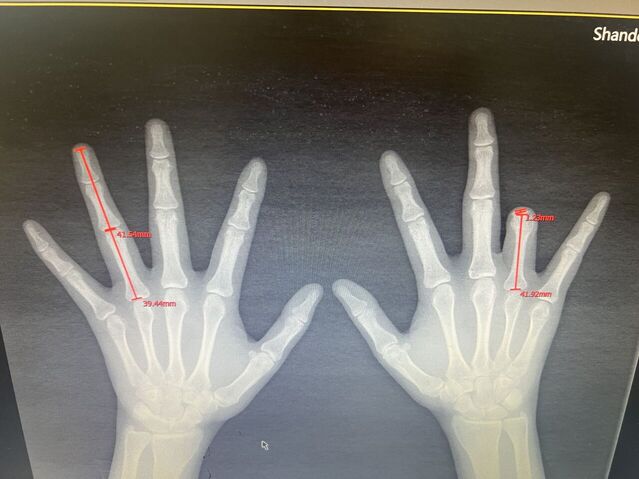

下面是一例示指再造,术后一年10个月随访

微信图片_20230930083837.jpg 微信图片_20230930083849.jpg 微信图片_20230930083851.jpg 微信图片_20230930083851_1.jpg

术后骨折愈合良好

微信图片_20230930075547_1.jpg 微信图片_20230930172958.jpg

术后1年10个月随访